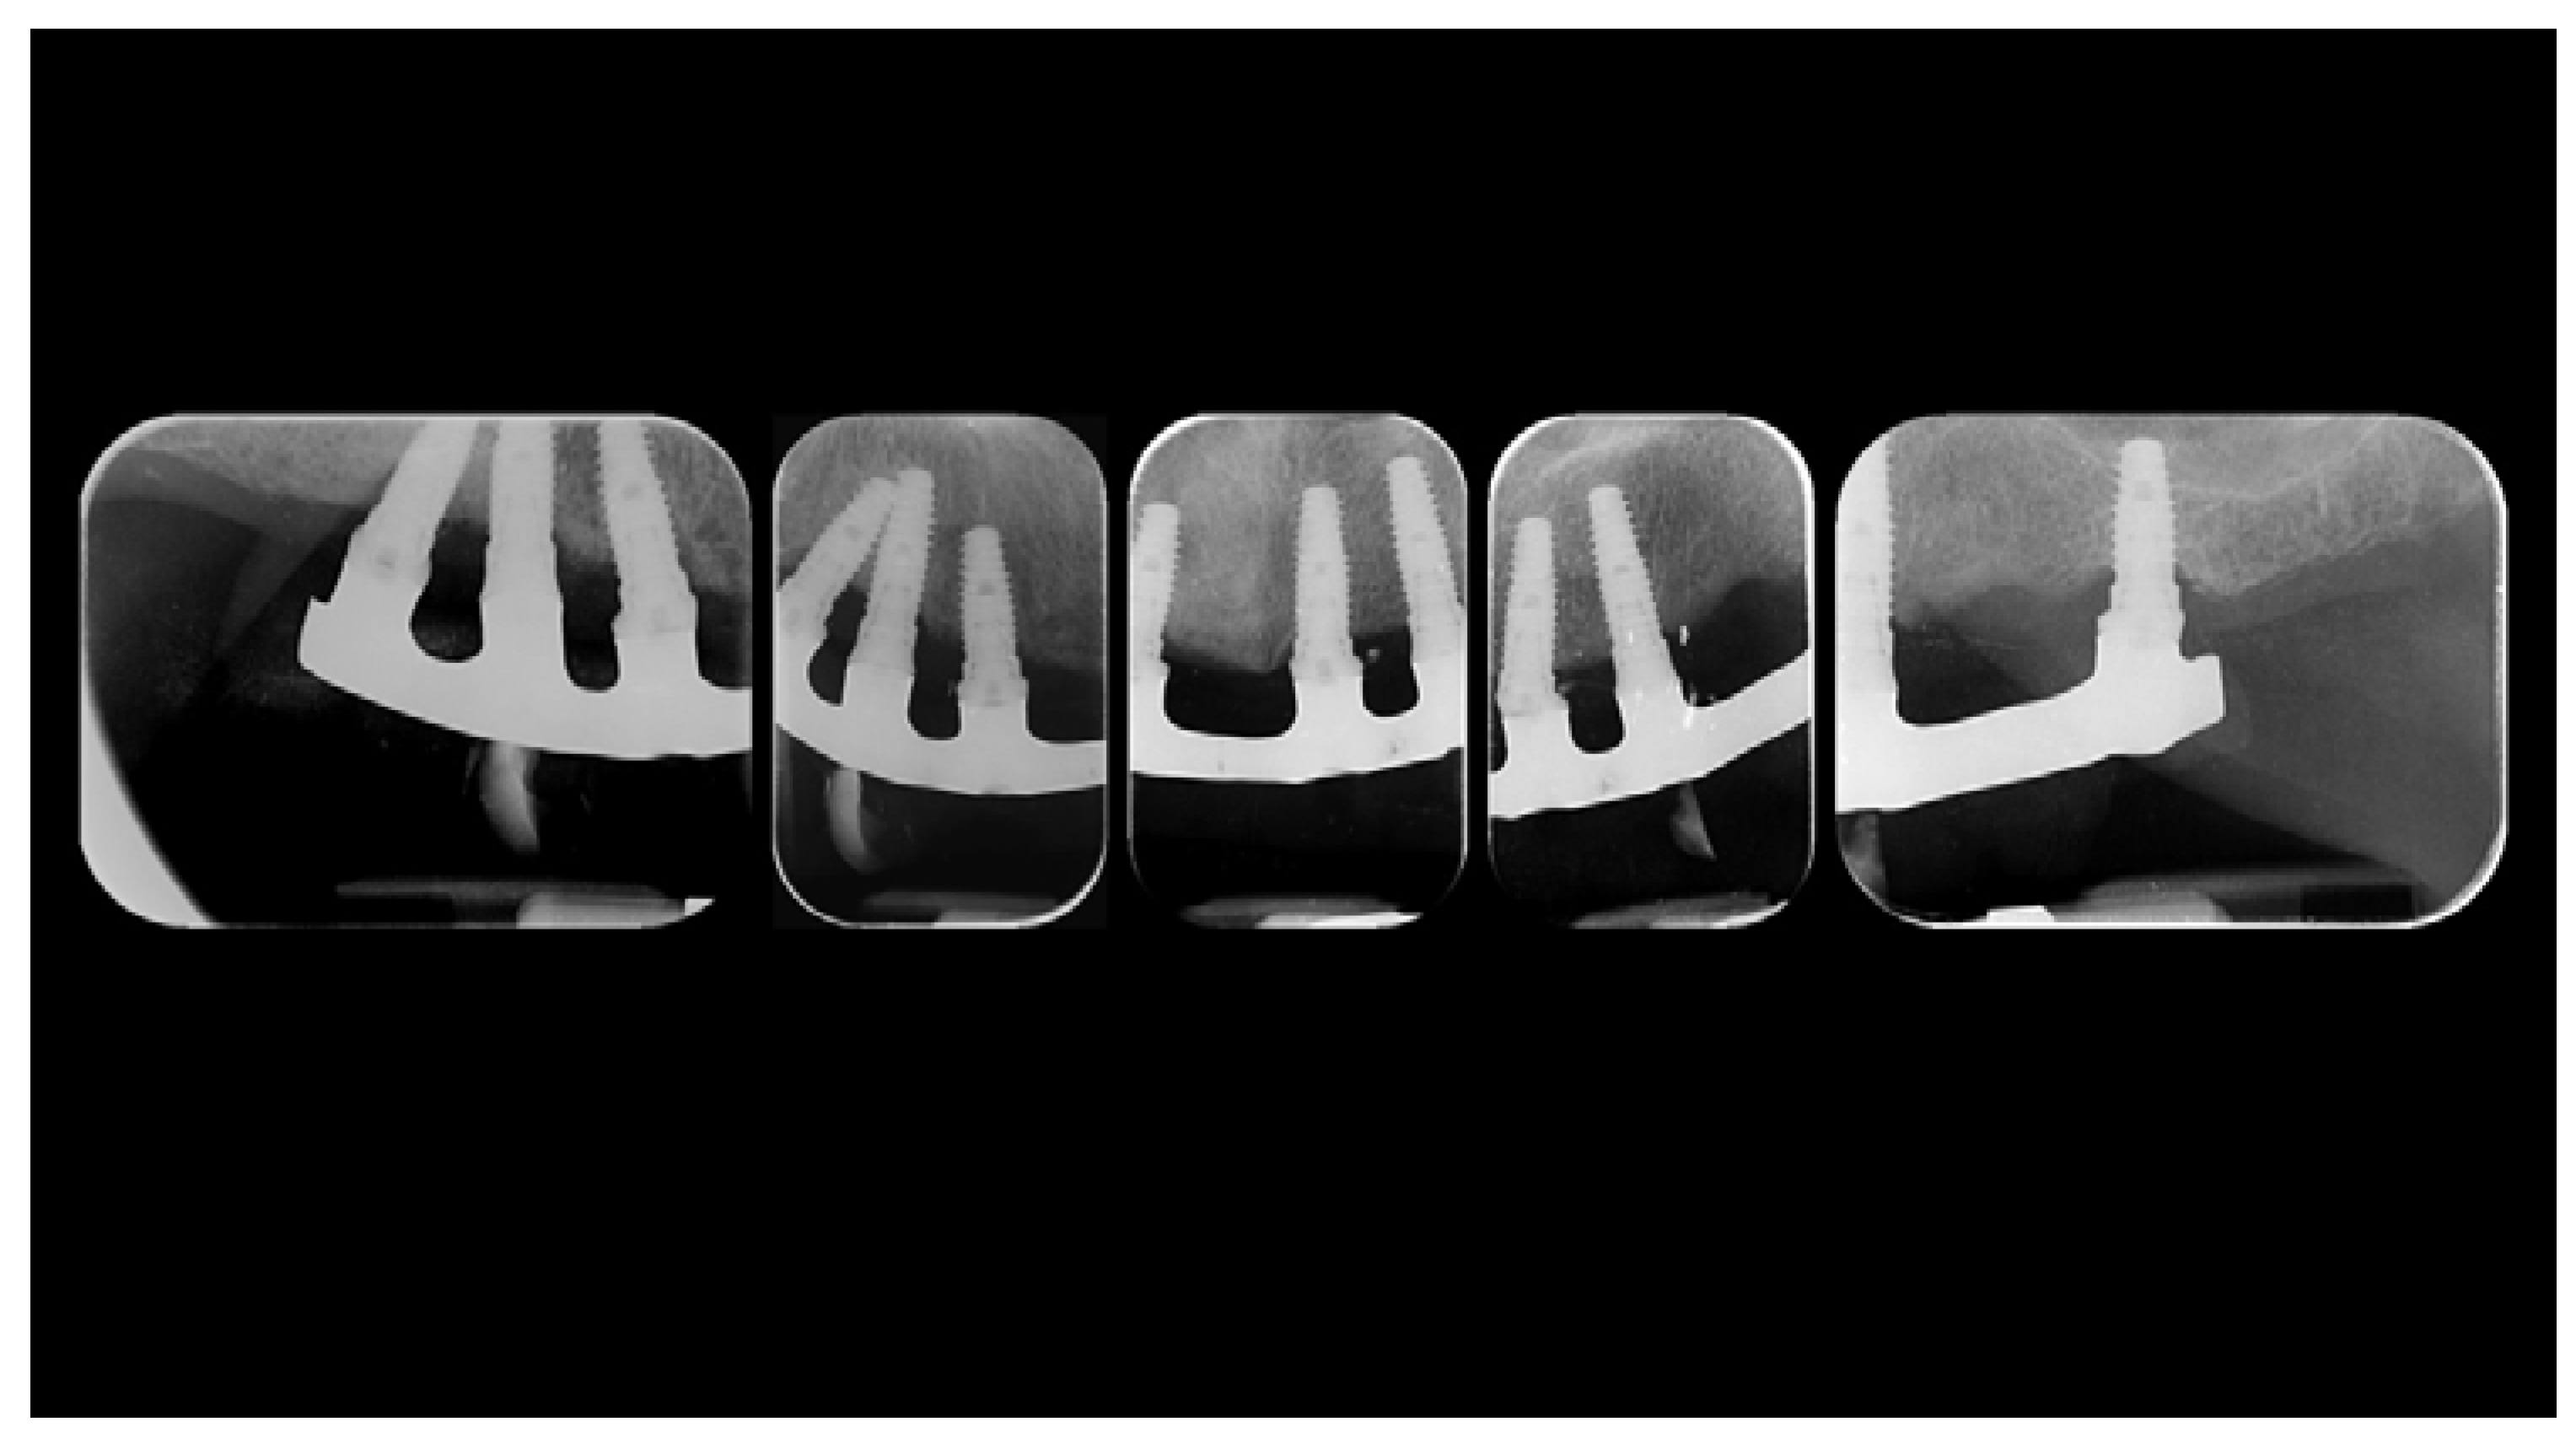

Figure 4.

Radiographic status of the previous restoration.